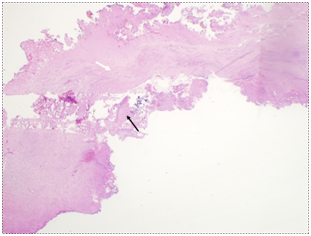

The CSD resection specimen collected intraoperatively was sent for pathologic examination and showed hyalinized and fibrotic tissue with chronic inflammation, consistent with old cesarean scar (Figure 3).

Figure 3 Patient 1, Pathology: Hyalinized cesarean scar (white arrow) and background uterine myometrium (black arrow). (H&E stain).

Figure 7 Patient 2, Pathology slides: a. The pathology figure 7a would roughly correspond to the red circle in figure 6: Low power view of resected fibrotic cesarean scar (white arrow) with placental site nodule (black arrow). (H&E stain) b. High Power view of placental site nodule (black arrow) showing hyalinization with degenerative implantation site trophoblast. (H&E stain).